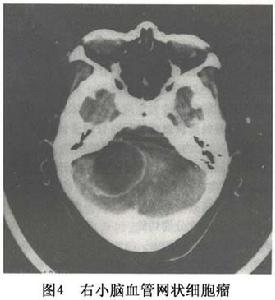

3.CT 典型表現為大囊內有小的瘤結節影,瘤結節和實性腫瘤呈等密度並均一強化,囊壁不強化。實質性腫瘤CT顯示為類圓形高密度影像密度不均勻;囊性者顯示為低密度,較其他囊腫密度高邊緣欠清晰,可見高密度結節突向囊腔內增強後囊壁密度多無變化,瘤結節呈均勻增強。腫瘤周圍可見低密度水腫帶。有人根據CT表現將之分為囊腫結節型、囊腫型、實體型及腦積水四型。